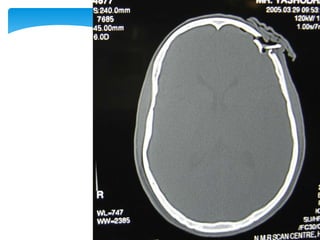

 Appearance of the normal structures

CT Scan

 Appearance ofthe normal structures CT Scan